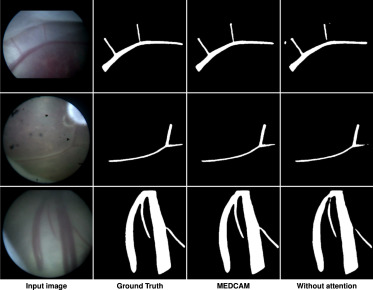

图10. MEDCAM模块对胎盘血管分割影响的定性比较。每行显示一个测试集示例。输入图像、真值、MEDCAM和无注意力模块的结果分别从左到右呈现。